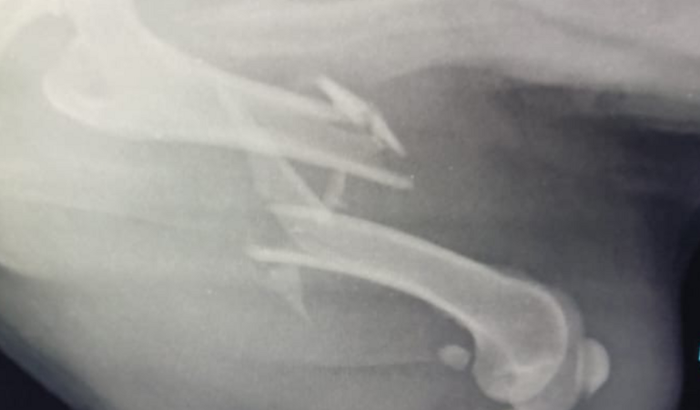

Olá Amigos!! Meu cachorrinho foi atropelado recentemente e teve uma fratura no fêmur e precisa passar por uma cirurgia de emergência para correção de sua patinha. Para isso preciso muito da ajuda de vocês!! O quanto puderem ajudar será muito bem vinda!! Desde já agradeço!